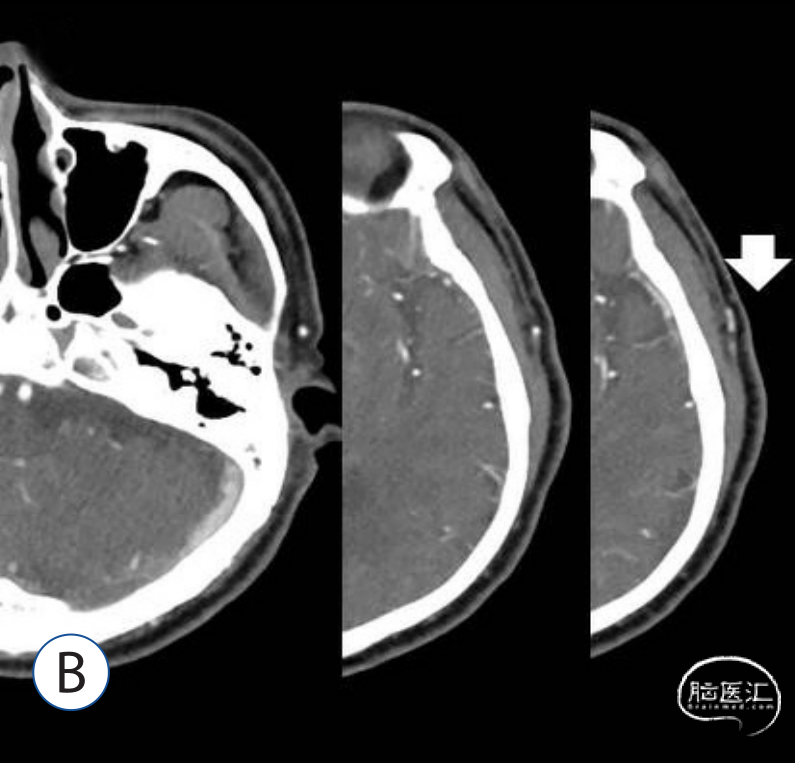

B:白色箭头表示颞浅动脉额叶和顶叶分支的分叉。

A:脑血管造影3D图像,显示位于右大脑中动脉分叉、右颈内动脉分叉两个动脉瘤。(疑为左侧)

B:脑血管造影3D图像,显示位于左脉络膜前动脉的动脉瘤。

C:黑色箭头表示颞浅动脉额叶和顶叶分支的分叉。

D:皮肤切口从颧弓上方约3cm的颞浅动脉分叉到内侧发际线呈曲线形。